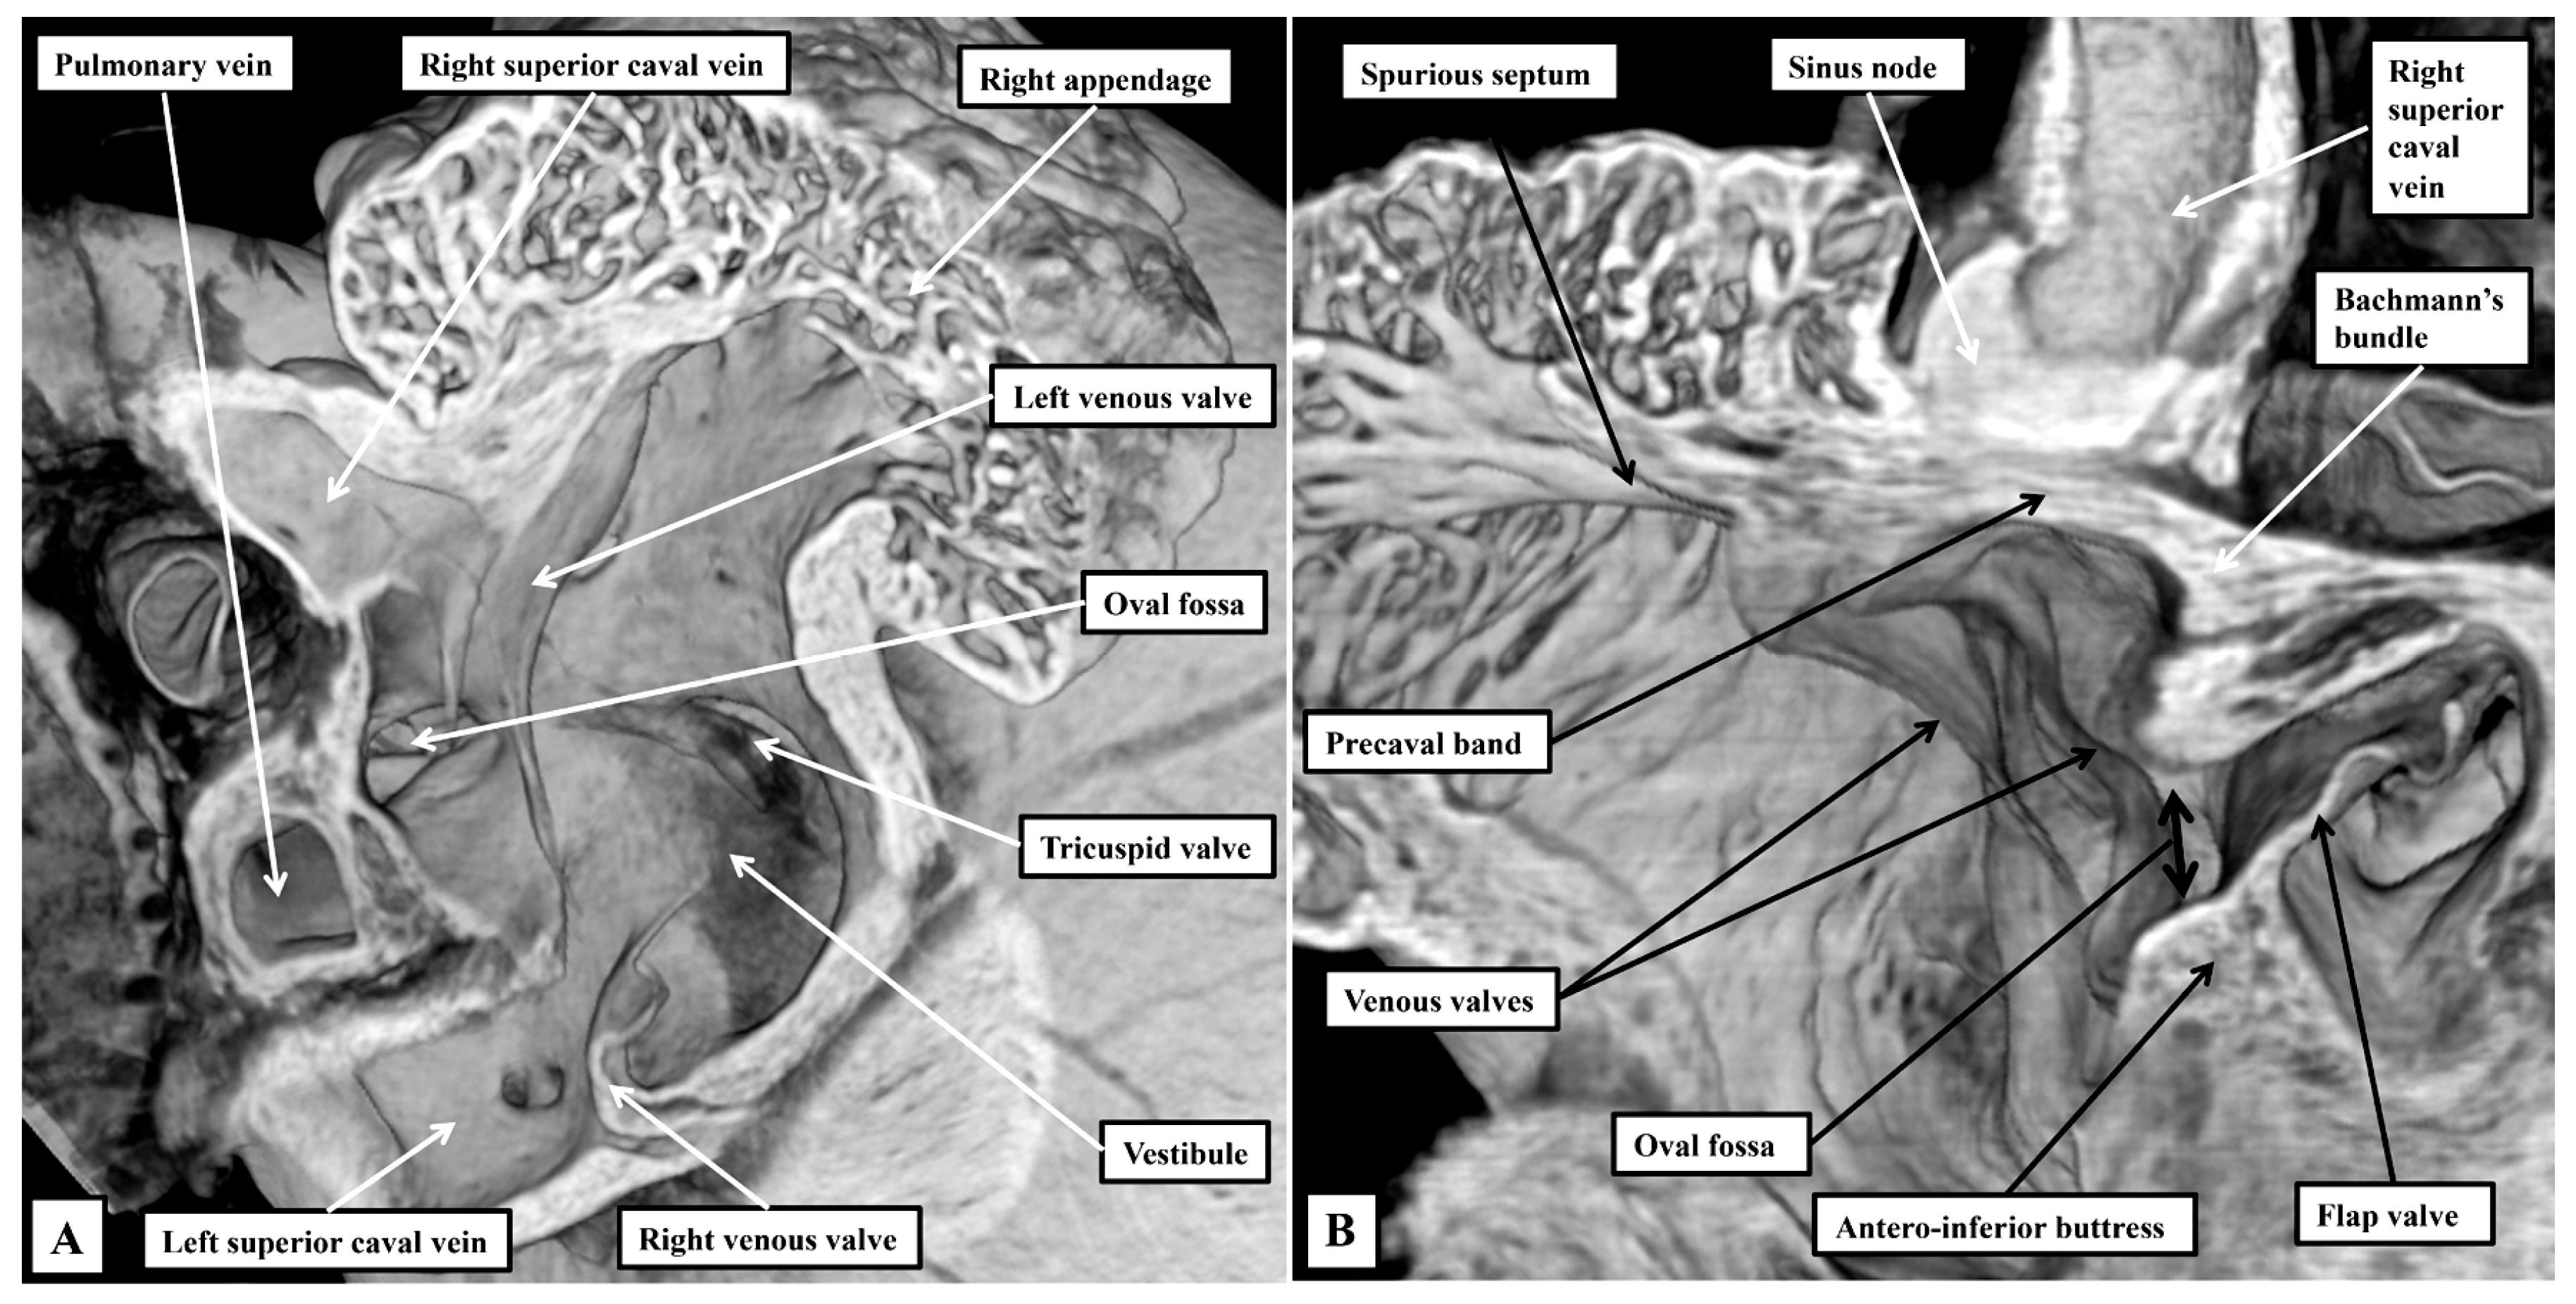

3.1. Gross Anatomy